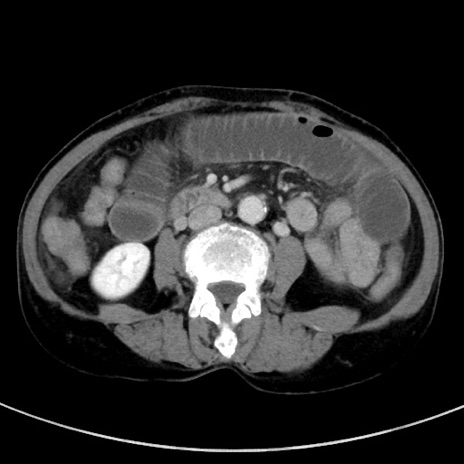

症例23(横断像)

冠状断像

【症例】70歳代女性

【主訴】下腹部痛・嘔吐

【現病歴】2日前より腹痛あり。昨日嘔吐あり。症状改善しないため来院。

【既往歴】胃GISTに対して胃部分切除後。

【身体所見】BT 37.1℃、BP 128/77mmHg、腹部:平坦・軟、下腹部に圧痛あり。

【データ】WBC 10200、CRP 0.31